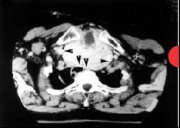

| 13:51, 12 בנובמבר 2012 | תצלוםתריס214.png (קובץ) |  |

24 קילו־בייטים | Motyk | 1 | |